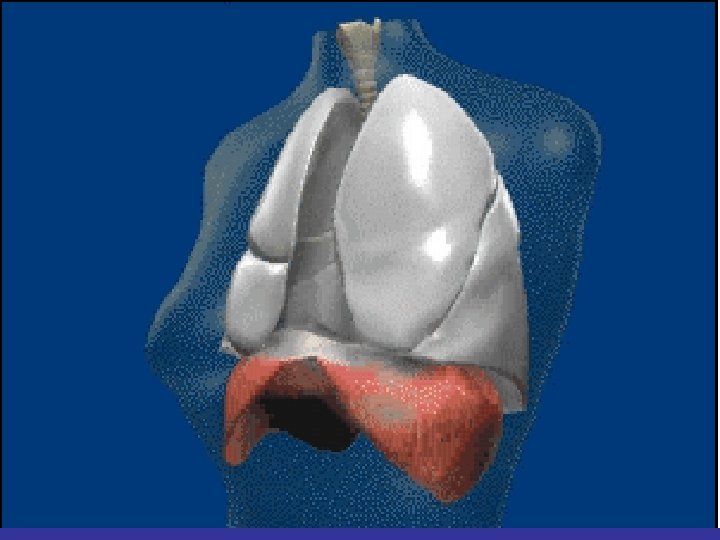

Lobes and Fissures